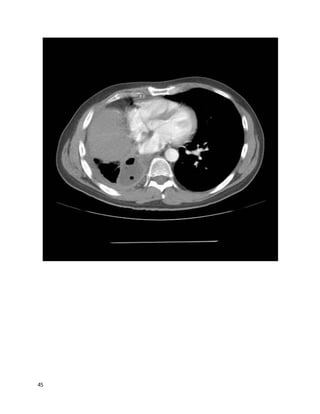

44

45

We feelthat C and A are the best answers.

This may be an empyema, and should be considered one until proven otherwise.

The contrast-enhancing, thickened visceral and parietal pleura on the CT images

are a good example of the "split pleura sign," suggestive of empyema or

Note that the large apparent effusion on scoutchest CT is nearly all due to the

opacity created by an elevated liver/diaphragm due to volume loss after his large

lung resection (see the liver at the level of the heart, on axial cuts). Ultrasound

would help avoid sticking this with a thoracentesis needle. The actual empyema

volume is small. (Cultures of the pleural fluid grew S. pneumoniae). This patient

got a chest tube; these images were actually post-chesttube removal (the original

CT showed an identical-sized fluid collection), which is likely responsible for the

gas bubbles in the effusion.